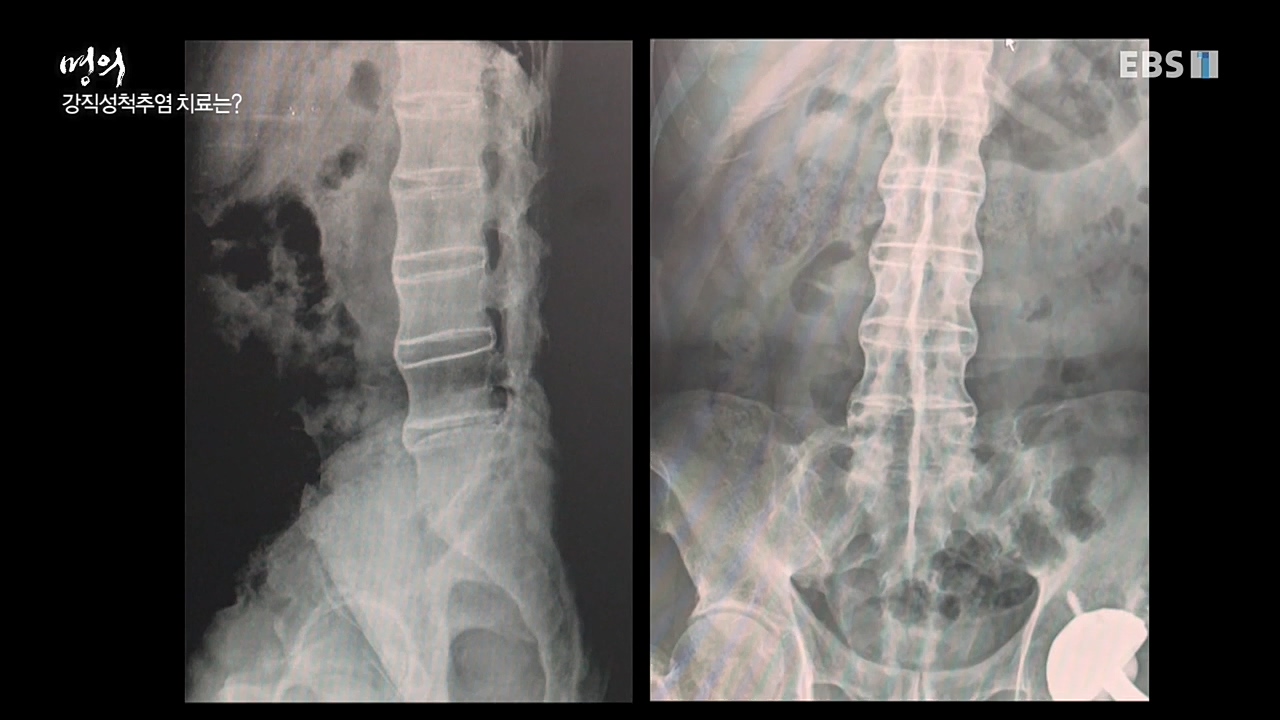

환자의 삶의 질 저해하는 강직성 척추염, 쎄레브렉스의 역할은? 방송을 보고나서_211214

소견 : 척추에 염증이 생겨 허리뼈가 굳는 강직성 척추염 ... 탐정이 된 의사 이지환은 10명의 역사적 인물을 선정했다. 현대의학이 발달되기 전 일...